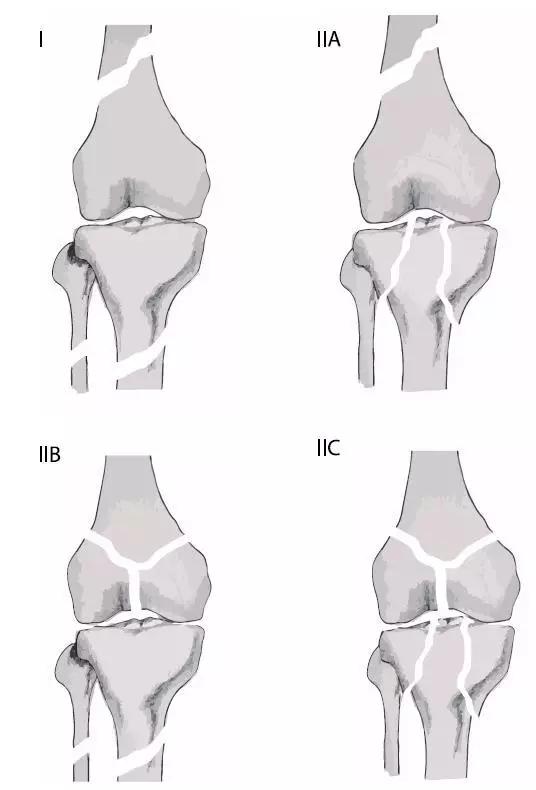

6. Pipkin 骨折

股骨头骨折。1957 年,Pipkin G 在文献中对其进行详细的描述并分型,至今仍在很多文献中被采用。

(来源:radiopaedia)

-

Ⅰ型:骨折块在圆韧带的下方;

Ⅱ型:骨折块在圆韧带的上方;

Ⅲ型:Ⅰ、Ⅱ两型任意一种伴股骨颈骨折;

Ⅳ型:Ⅰ、Ⅱ两型任意一种伴髋臼骨折 。